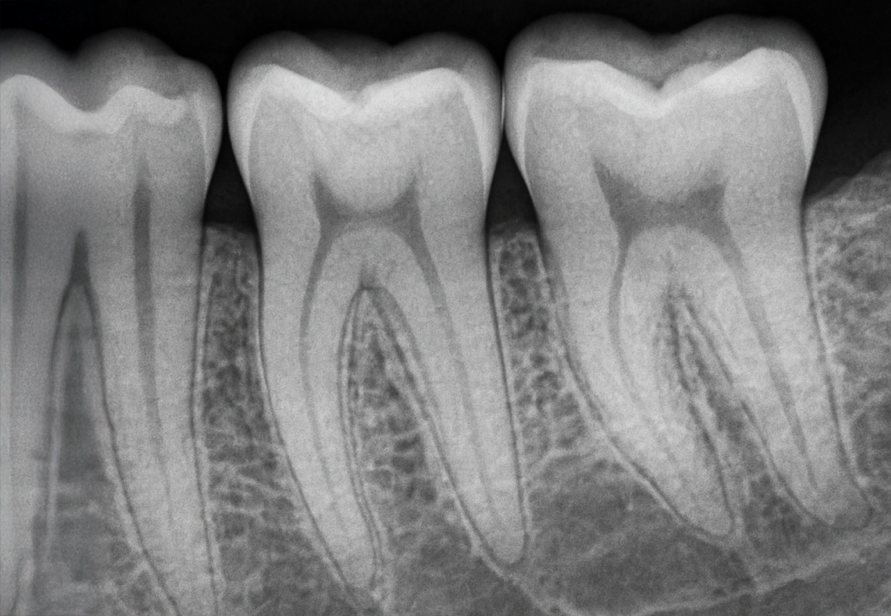

Le cabinet est spécialisé dans la prise en charge des pathologies de la racine dentaire. Nous réalisons exclusivement des soins endodontiques sur prescription : consultation diagnostique, traitement ou retraitement des canaux, chirurgie endodontique et suivi post-opératoire. Chaque soin est réalisé sous anesthésie locale, avec microscope opératoire, dans un environnement technique de haut niveau. Nous assurons également un lien étroit avec votre dentiste traitant pour garantir une continuité de soin optimale.

L’endodontie est la spécialité qui traite l’intérieur de la dent, notamment le nerf. En cas d’infection ou de douleur, elle permet de nettoyer, désinfecter et préserver la dent grâce à un traitement ciblé des racines. Ces soins précis sont réalisés sous anesthésie locale et microscope opératoire, dans un environnement strictement aseptisé.